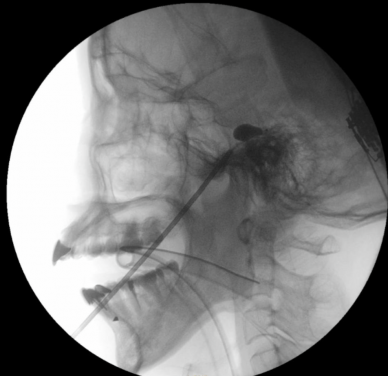

PBC is an interventional technique designed to alleviate pain associated with the trigeminal nerve, which is responsible for facial sensation. The procedure involves inserting a tiny balloon through the cheek into the trigeminal ganglion near the base of the skull and inflating it with contrast medium to gently compress the nerve’s pain fibres. Proper placement is confirmed by fluoroscopic imaging, which shows the characteristic pear-shaped appearance of the balloon.